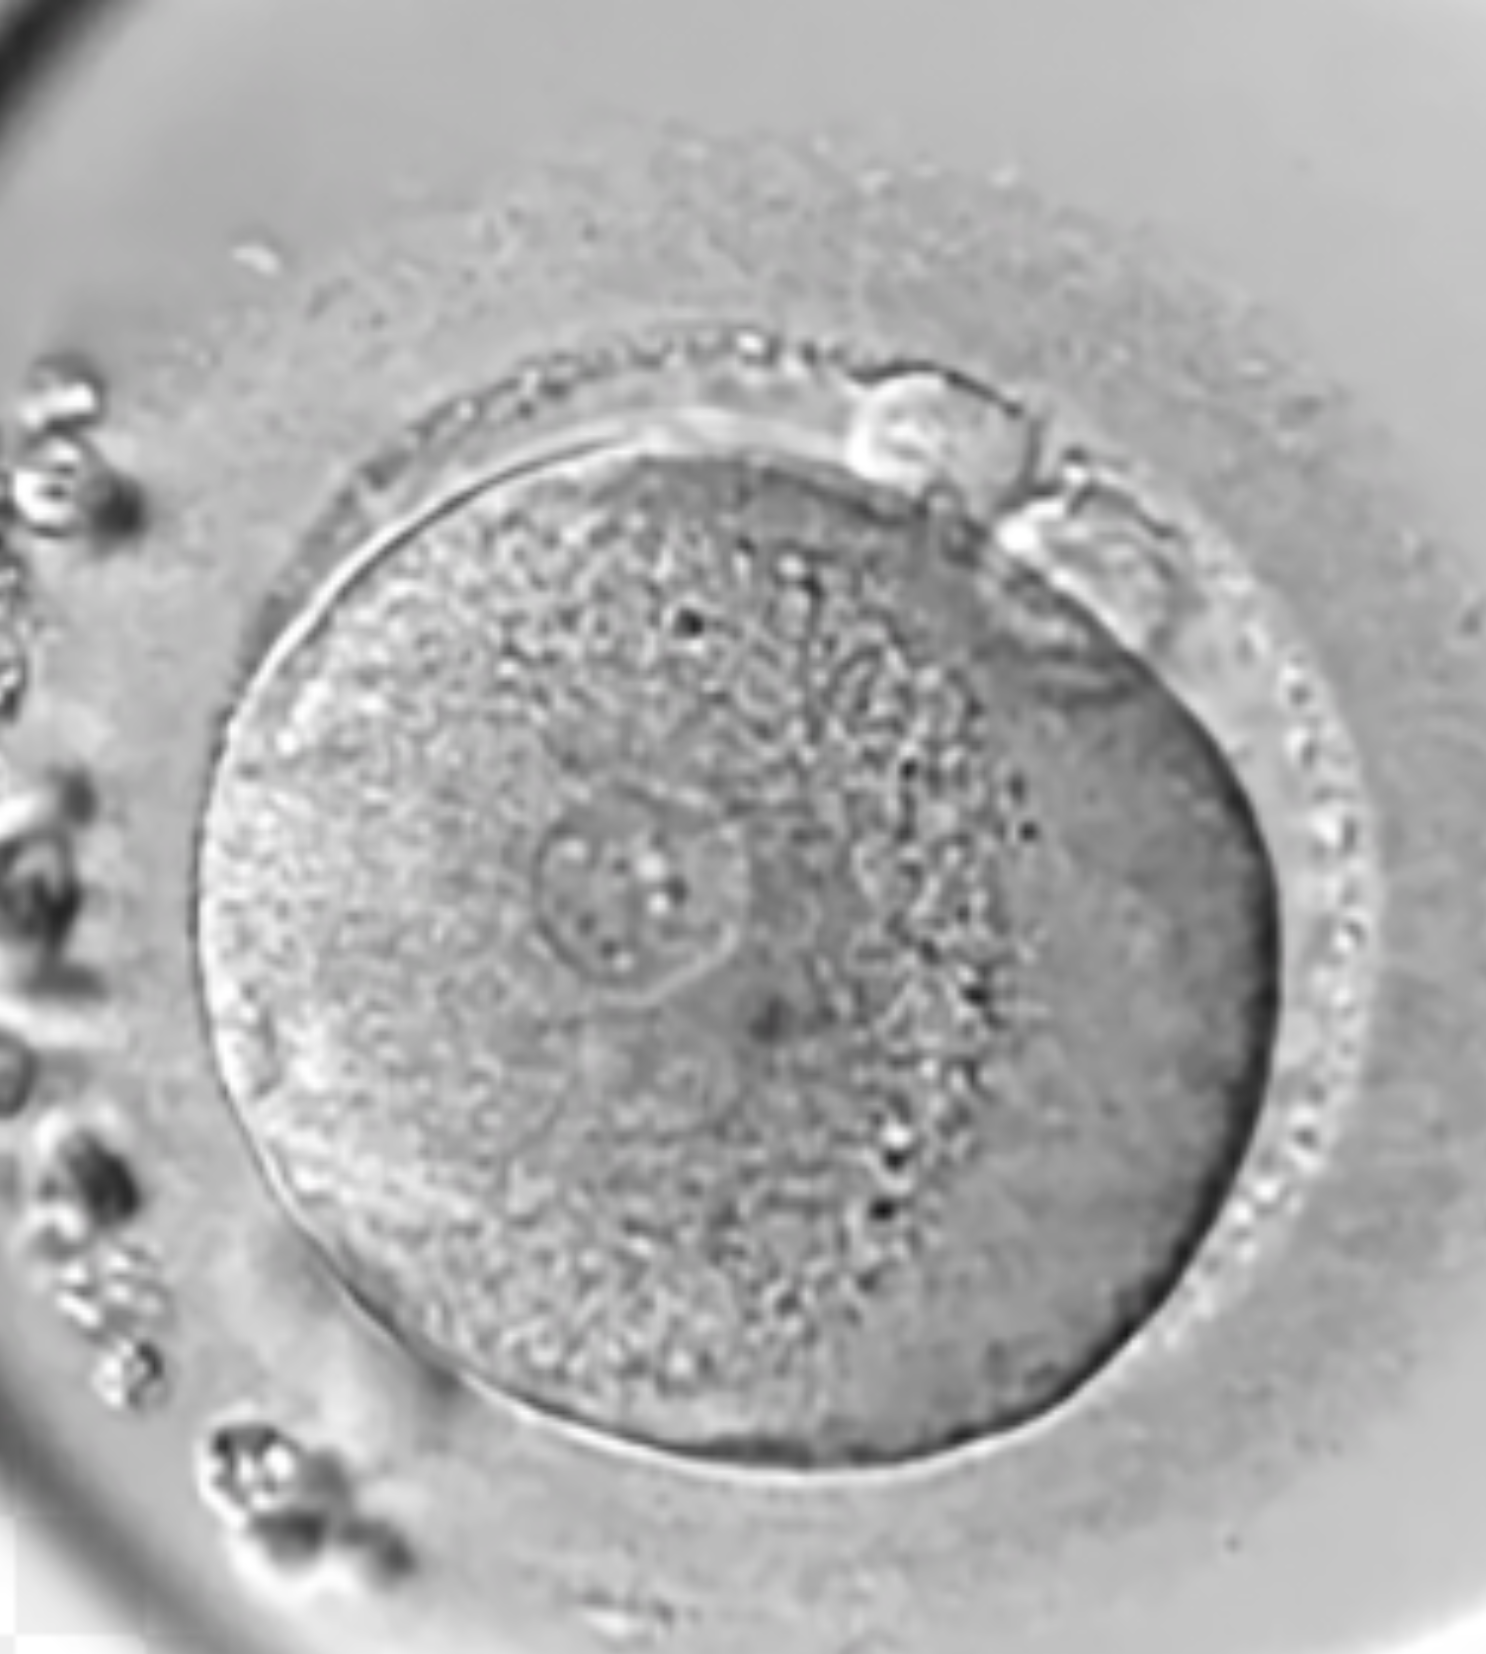

The 3PN

This is a clear 3PN. The PN’s are all the same size. These embryos are impossible to use without PGT-A testing to confirm how much DNA they have in them. True 3PN’s (with 3 copies of DNA) can result in dangerous partial molar pregnancies.